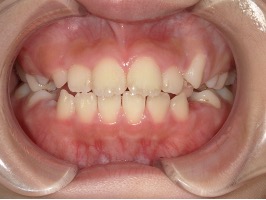

| 年齢・性別 | 8歳9ヶ月の女児 |

|---|---|

| 主訴 | 歯並びの乱れを気にされて来院された患者様です。将来的なスペース不足と歯のねじれ(翼状捻転)が懸念されました。 |

| 治療期間・回数 | 2年10ヶ月・19回 |

| 費用 | 430,000円(税別) |